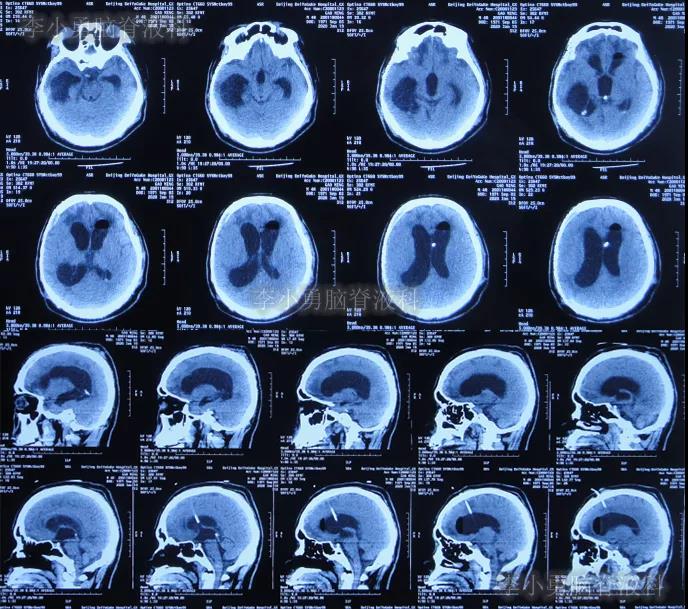

2019年4月2日(第4家医院治疗192天即脑室腹壁外引流术后176天),按计划进行钛网颅骨修补术,术后当天查头颅CT示颅骨修补术后(图-3)。

图-3:2019年4月2日头颅CT

颅骨修补术后7天即2019年4月9日,查头颅CT头颅示颅骨修补术后,仍脑积水(图-4)。

图-4:2019年4月9日头颅CT